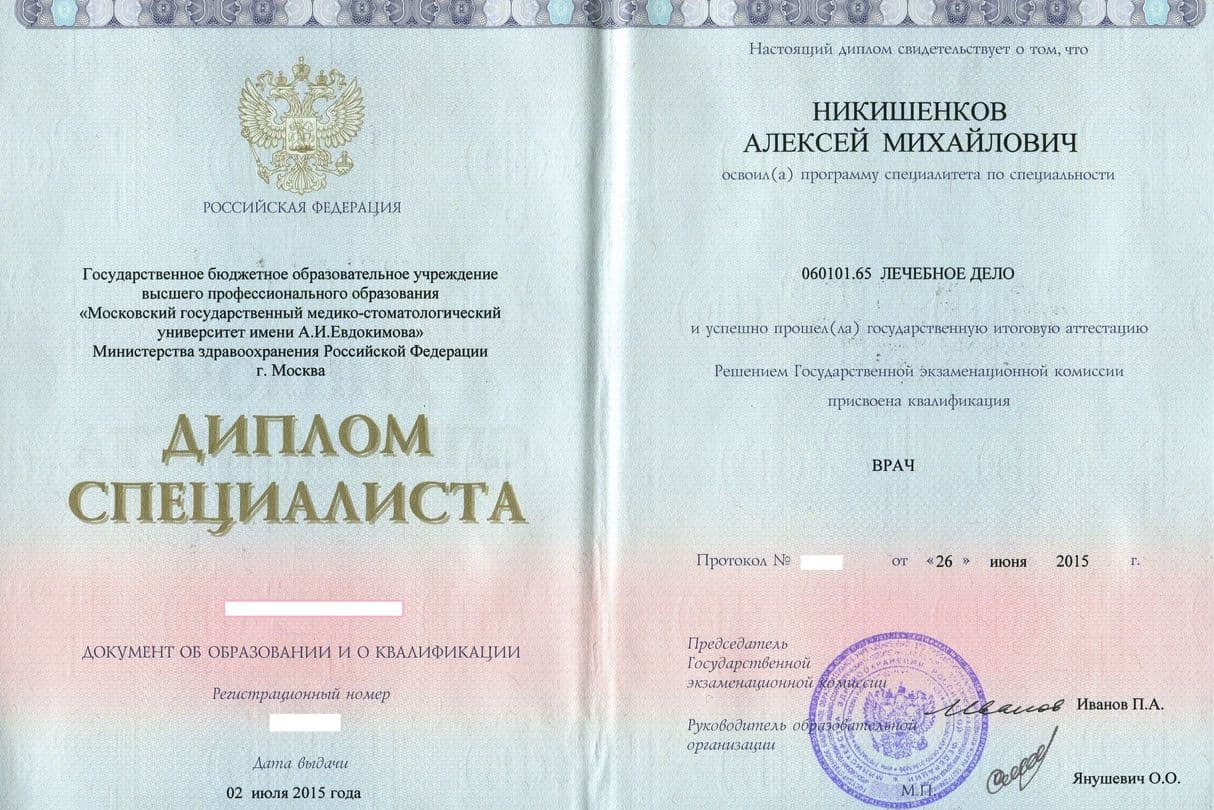

Алексей Михайлович

Никишенков

Если вы находитесь на этой странице, вероятно у вас есть нерешенные вопросы, связанные со здоровьем, состоянием легких, компьютерной томографией, результатами анализов и т.д. Либо вы врач и хотите пройти у меня обучение